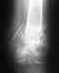

3 мая после ДТП у меня сложный перелом дистального метаэпифиза левой б/б кости, внутренней лодыжки, оскольчатый перелом наружной лодыжки с подвывихом стопы.

7.05.08 проведена операция: открытая репозиция, М.О.С. внутренней и наружной лодыжек слева. ТАФ сустава.

При обращении на консультацию врачи рекомендуют операцию артродез голеностопного сустава, как единственно возможный вариант. Р/снимки и выписка прилагаются.

Основная часть смещенных фрагментов суставной площадки большеберцовой кости не вправлена и не была фиксирована. Все уже срослось в неправильном положении. Восстановить форму суставной поверхности и трудно, и, главное, это не обеспечит здоровый сустав. Вариант с артродезом тут вполне уместен. Способность нормально ходить как раз артродез и обеспечит.